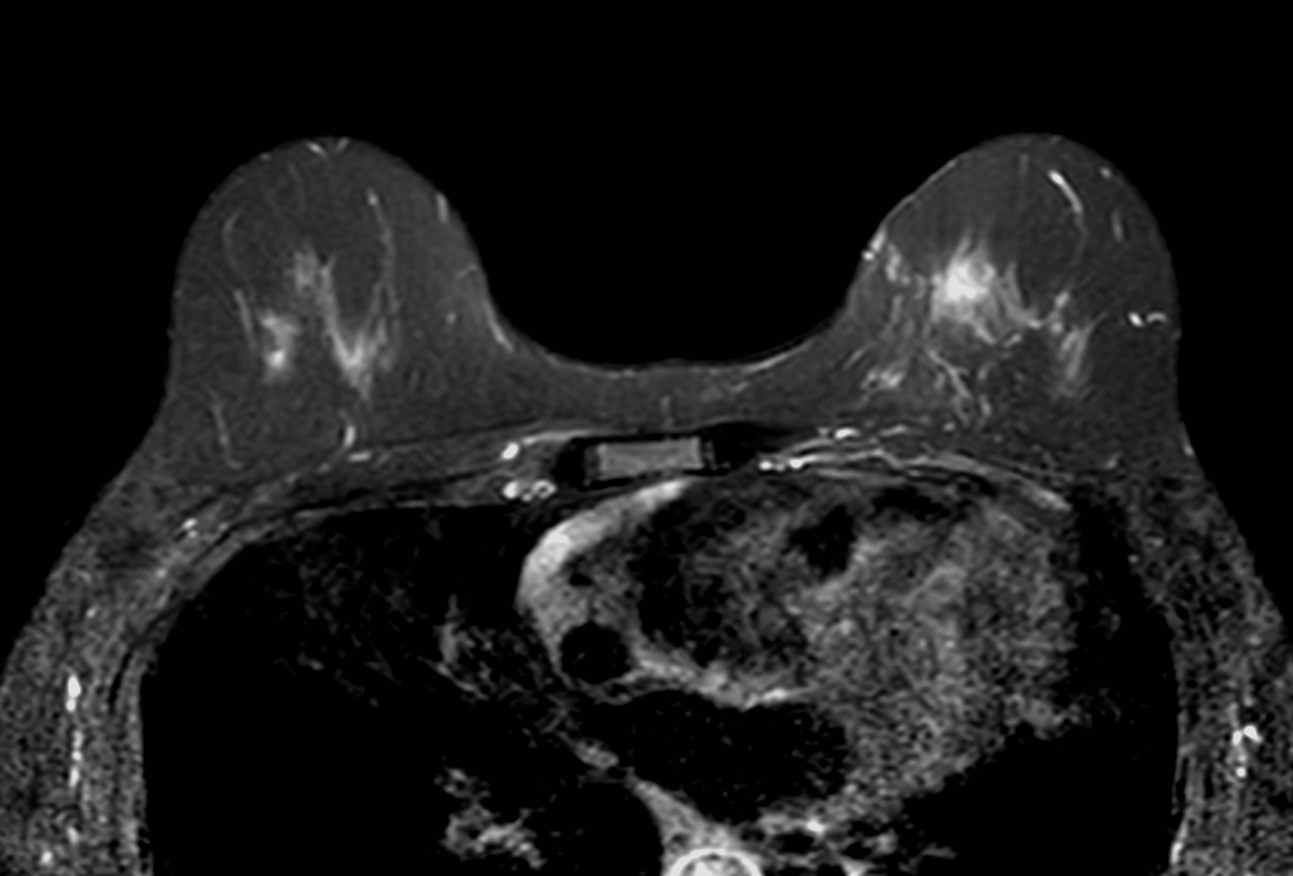

Breast lesion

Axial T2w SPAIR